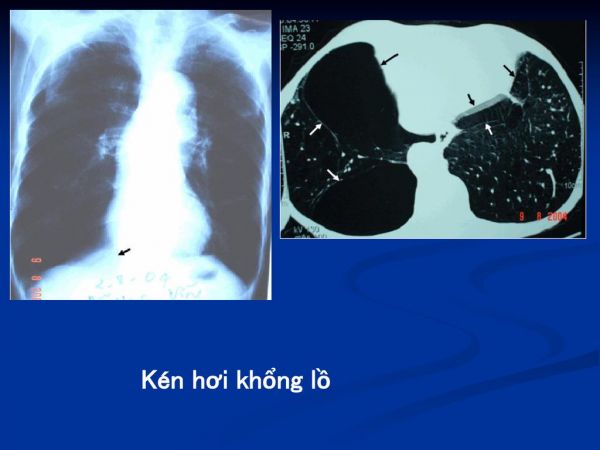

Kén hơi khổng lồ phổi trái

Nhưng bóng khí khổng lồ bắt đầu ra trên bản sắc riêng. Trên x-quang ngực chúng xuất hiện như những thực thể phần nào độc lập với cấu trúc bình thường còn lại của phổi bị ảnh hưởng, cách nhau bởi một mỏng, sợi, màng không đều. Khi đầy không khí và phát triển, các bóng khí khổng lồ cũng có thể bị tràn dịch để tạo ra sự pha trộn truyền nhiễm. Không chỉ có các bóng khí khổng lồ gây cản trở chức năng của phổi; nó có thể gây áp lực lên phổi và gây trở ngại cho chức năng thích hợp của nó. Vì vậy, ngay cả các mô không bị ảnh hưởng bởi căn bệnh trở nên kém hiệu quả.